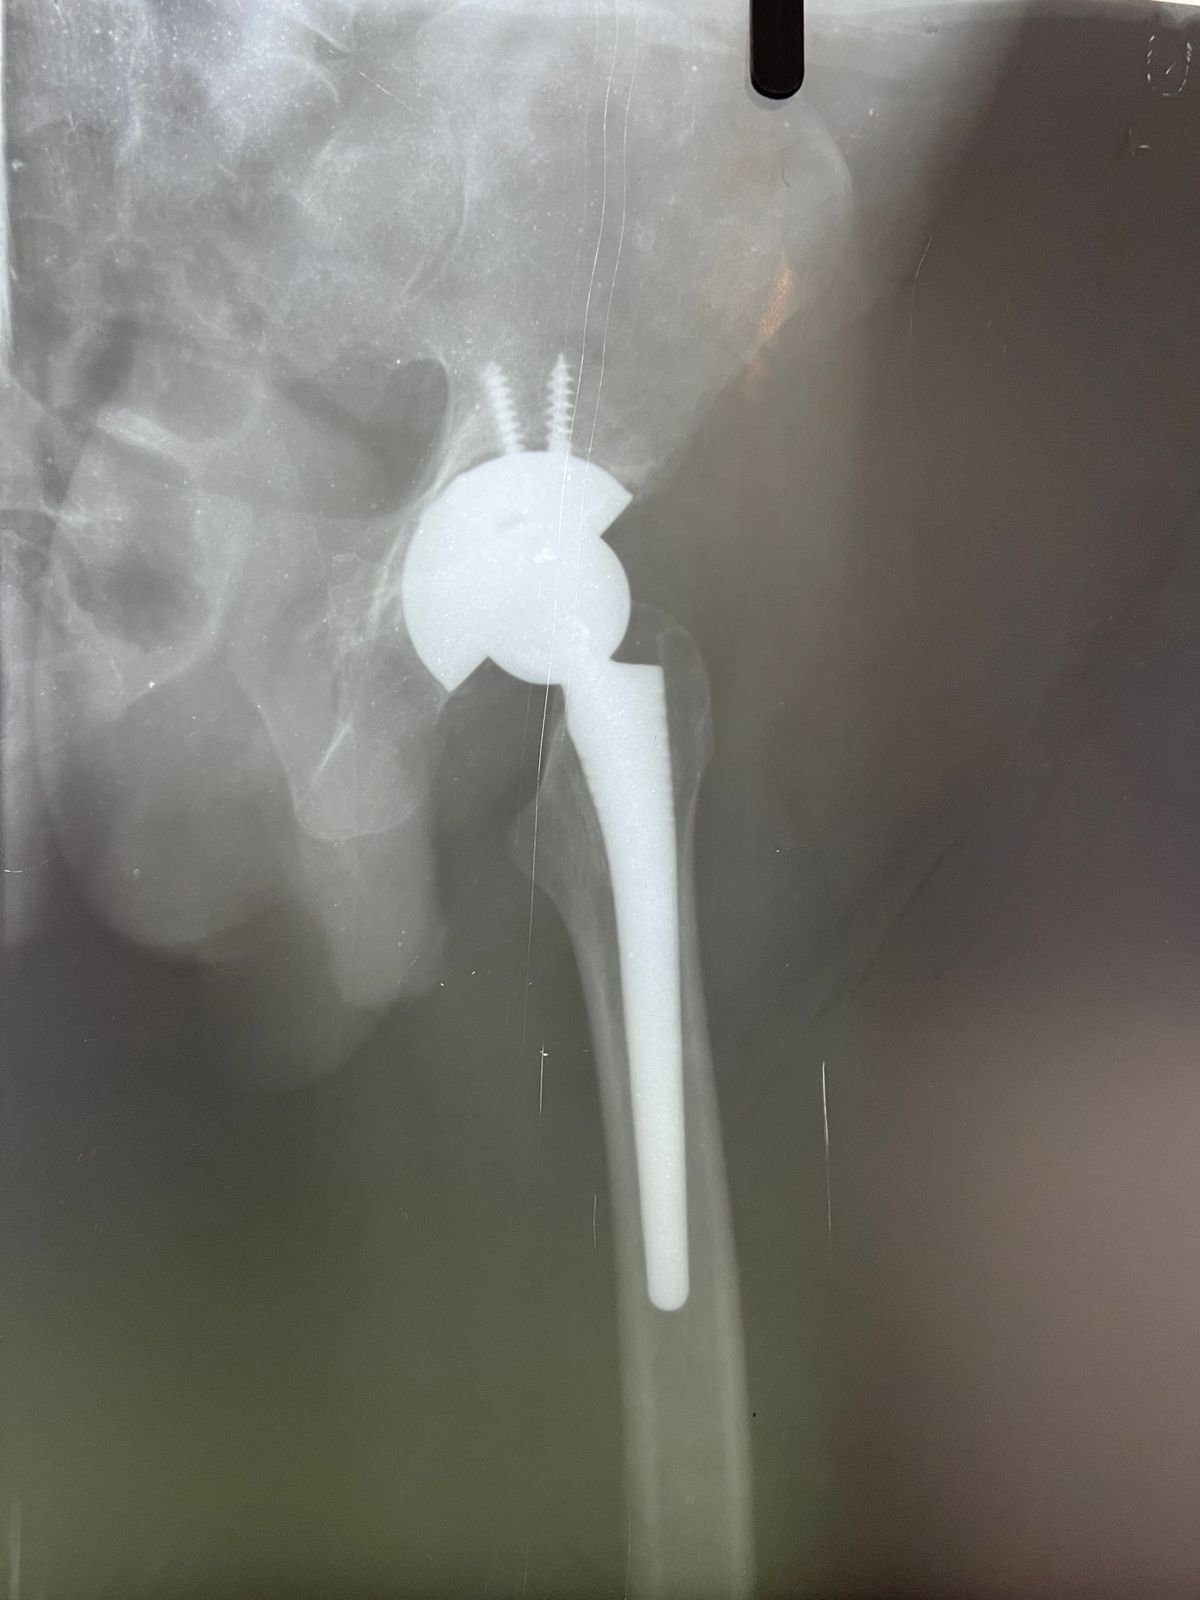

plaster & operation | Total Hip replacement case |